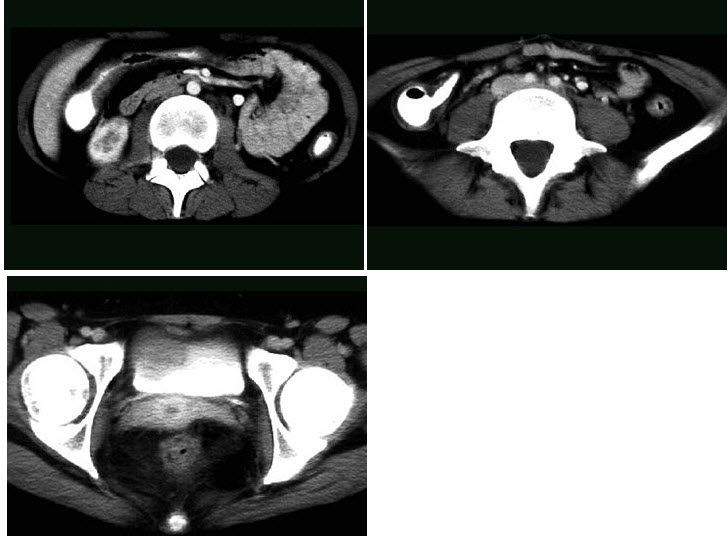

19、多项选择题

女,44岁,突发性胁腹部绞痛并向会阴部放射伴血尿一次,CT扫描如图所示,下列说法正确的是()

A.右侧肾盂肾盏扩张

B.右输尿管中上段扩张

C.右输尿管内可见沿输尿管走行的高密度影

D.右输尿管结石

E.左肾输尿管未见异常

点击查看答案